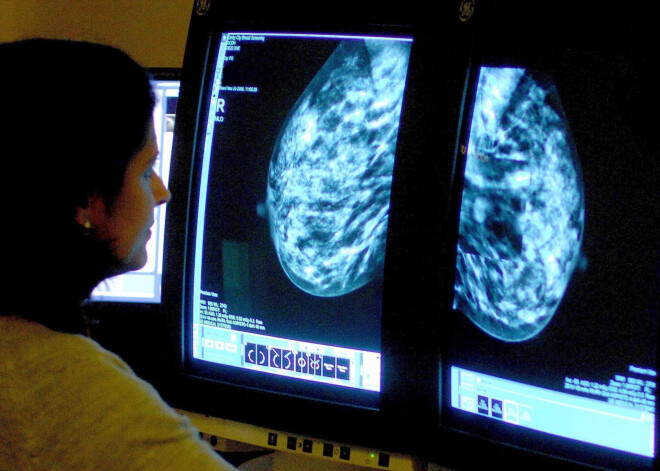

Radiologi ASV ziņo par Covid-19 vakcīnas efektu, kas var lieki satraukt tieši sievietes

Radiologi ASV ziņo par potenciālu Covid-19 vakcīnas blakusefektu – limfmezglu pietūkumu zem paduses. Šis pietūkums uzrādās mamogrammās, tāpēc sievietēm uzreiz pēc vakcīnas saņemšanas neiesaka veikt mamogrāfiju, citādi var rasties maldinošs priekšstats par veselības problēmām, ziņo CNN.

Veicot krūšu mamogrāfiju, iekaisušie limfmezgli tajā uzrādās kā balti plankumi.

Gadījumos, ja mamogrāfijā konstatēts limfātisko mezglu iekaisums padušu apvidū, sievietēm tiek veikta krūts audu biopsija, jo palielinātie limfmezgli var būt krūts vēža rādītājs. Tomēr, kā norāda radiologi, šāda aina sievietēm nereti uzrādās pēc Covid-19 vakcīnas saņemšanas, un lielākoties par to nevajadzētu satraukties.